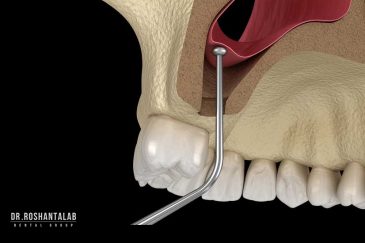

🔸جراحی پیشرفته نظیر سینوس لیفت

بهره مندی از دانش علمی و تجربه بالای موسس و جراحان این کلینیک، همچنین امکانات و تجهیزات به روز و کارآمد از جمله ویژگی های منحصر به فرد این کلینیک است. همچنین با ارائه خدمات درمانی با کیفیت و هزینه مناسب دندانپزشکی در رشت، تهران، اصفهان و استانبول ترکیه توانسته است در این سال ها لبخند رضایت بر صورت مراجعه کنندگان عزیزمان بگذارد.